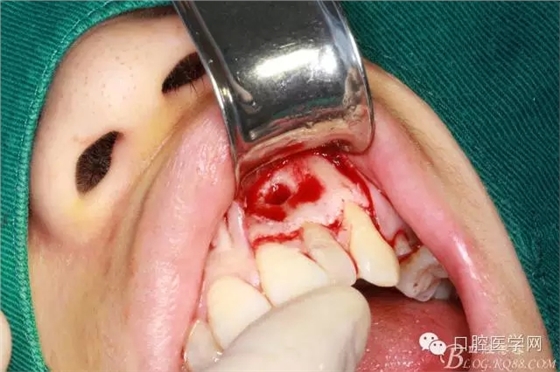

去 骨

可見囊腫

刮凈囊腫